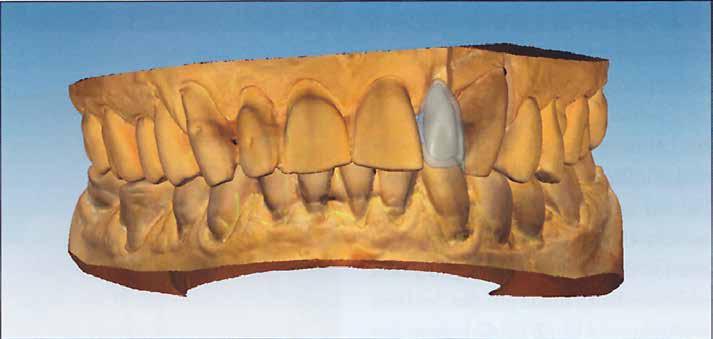

Az ideiglenes fogsor elkészítéséhez a még meglévő fogakat törölni kellett a virtuális modellről (3. ábra). Ehhez a szoftver megfelelő eszközöket biztosít. A modellanalízis közben a szoftver lépésről lépésre vezet minket. Az anatómiai jellemzőket megjelöljük és a fogsor kiterjesztésének paramétereit rögzítjük (4. ábra). Az állkapocsviszony meghatározása alapján a függőlegest 5,5 mm-rel megemeltük (5. a ábra). A Digital Denture Full Arch könyvtár segítségével megtörtént a megfelelő fogforma kiválasztása (Phonares® II B71-L50-N3)

(5. b ábra)

Pink, Pink V, 34V) (8. ábra). 2. ábra: A még meglévő fogak komoly károsodása. 3. ábra: A még meglévő fogak virtuális extrahálása. 4. ábra: Virtuális modellanalízis. 5. ábra: A harapási magasság megemelése 5,5 mm-rel és a fogforma kiválasztása a Digital Denture Full Arch könyvtár segítségével.